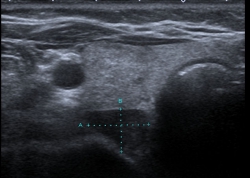

The diagnosis is often discovered incidentally during routine blood work by an elevated calcium level. By detection at an earlier stage of the disease, patients are often without definite symptoms, but severe prolonged primary hyperparathyroidism can lead to kidney stones, osteoporosis and gastric ulcers ("stone, leg and stomach pein"). For localization diagnosis of the altered parathyroid gland, an ultrasound and, if necessary, an additional parathyroid scintigraphy are performed.

Parathyroid adenoma on ultrasound Parathyroid adenoma